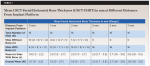

At T3, the mean radiographic marginal bone level (MBL) change of -0.3 ± 0.3 (-0.7 to 0) mm was noted on the mesial aspect of the implant, while -0.5 ± 0.5 (-2.0 to 0) mm was noted on the distal aspect of the implant, yielding an overall average MBL change of -0.4 ± 0.3 (-1.0 to 0) mm. There was no statistically significant difference in the mean MBL between the U-shaped (-0.6 mm) and V-shaped (-0.4) groups (P = .79). At T3, CBCT evaluation showed a mean facial marginal bone level (FMBL) of -0.6 ± 0.8 (-2.1 to 0.5) mm in relation to the implant platform. Except for a single site at the 2 mm level, facial horizontal bone thickness (CBCT-FHBT) at all sites in all levels was ≥1.5 mm (Table 1).

The mean overall changes of facial implant mucosal thickness (FIMT) from T1 to T2, facial implant mucosal level (FIML) from T0 to T3, and midfacial bone sounding (MFBS) from T1 to T3 were 1.2 ± 0.5 (1.6 to 2.9) mm, -0.4 ± 0.4 (-1.6 to 1.0) mm, and 6.0 ± 1.4 (4.0 to 8.5) mm, respectively (Table 2 through Table 4). Comparisons of tissue changes between different parameters (thick vs thin phenotype, V- vs U-shaped facial bone wall defect, and surgery with vs without full-thickness flap reflection) also are presented in Table 2 and Table 3. Regardless of phenotype, defect shape, or surgical technique, the mean FIMT values at T2 were comparable (2.3 mm to 2.4 mm), and all MFBS measurements at T3 were between 3 mm and 4 mm (Table 2 and Table 4). The mean FIML change of -0.4 mm and MFBS change of 6.0 mm translates to a mean vertical facial hard tissue gain of 5.6 mm.

The significance of a C-BG at the time of IIPP in maintaining facial mucosal level in the presence of a facial bone wall defect is also a point of discussion. Typically, it takes months for bone cells to migrate from the surrounding socket walls to encase or replace the grafted bone material within the extraction socket.23 Therefore, the initially grafted bone only serves as a matrix to support the soft tissue until vital bone formation occurs. During the early healing time, the most coronal portion of the bone at the facial entrance of the extraction socket will serve to maintain the FIML until grafted bone matures. In this study, facial contour bone grafting over the implant and facial bone wall defect (T1) resulted in a mean MFBS change of 3.5 mm ± 0.4 mm (T3), suggesting that the particulate bone graft material turned into solid, stable bone over time. It is interesting to note that regardless of tissue phenotype, defect shape, or whether the surgical procedure was done with or without flap reflection, all of the MFBS measurements at T3in all sites were between 3 mm and 4 mm (Table 3), indicating that the technique performed in this study could yield a predictable result. Moreover, because the platforms of the implants in this study were placed about 3 mm apical from the facial mucosal margin, the radiographic bone measurement from the implant platform (mean CBCT-FMBL [-0.7 mm]) and the bone sounding measurement (mean MFBS [3.5 mm]) confirmed that the facial bone was regenerated almost to the level of the implant platform. At T3, the mean FIML change of -0.4 mm and mean MFBS change of 6.0 mm also translate to the mean vertical facial hard tissue gain of 5.6 mm.

The importance of the facial-palatal implant position on the FIML cannot be overstated. A facially positioned implant can exhibit gingival recession three times greater than that of a palatally positioned implant.24 In general, from an incisal view, the implant should be placed palatally (engaging palatal bone) and within the confines of the extraction socket aligned with the arch form. Especially in situations where a facial bone wall defect is present, a palatally positioned implant allows for facial bone grafting to achieve appropriate vertical and horizontal underlying bone support for optimal peri-implant soft-tissue architecture. In the present study, CBCT assessment showed a mean FHBT of 0.6 mm, 1.5 mm, 1.9 mm, 2.5 mm, 2.7 mm, and 2.9 mm at 0 mm, 1 mm, 2 mm, 3 mm, 5 mm, and 7 mm apical to the implant platform, respectively. Creating an adequate bone thickness with a contour bone graft over the facial aspect of the implant is significant, as Monje et al reported that the chances of implant marginal bone loss were significantly reduced with a minimal facial bone thickness of 1.5 mm,25 thereby lessening the risk of surface contamination and peri-implantitis.26,27